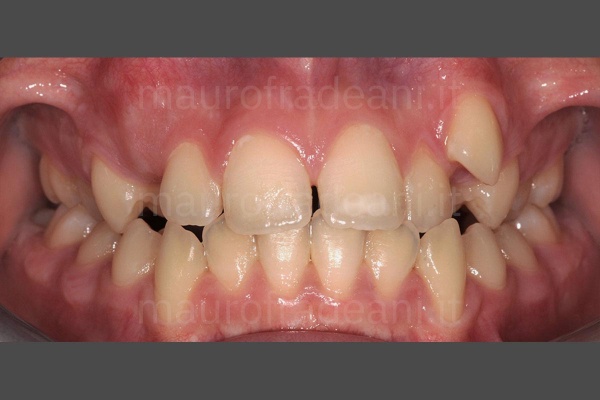

Oltre all’ortodonzia fissa con i classici “brackets”, negli ultimi anni si ricorre sempre più frequentemente all’ausilio di mascherine trasparenti, altrettanto efficaci ma esteticamente meno invasive.